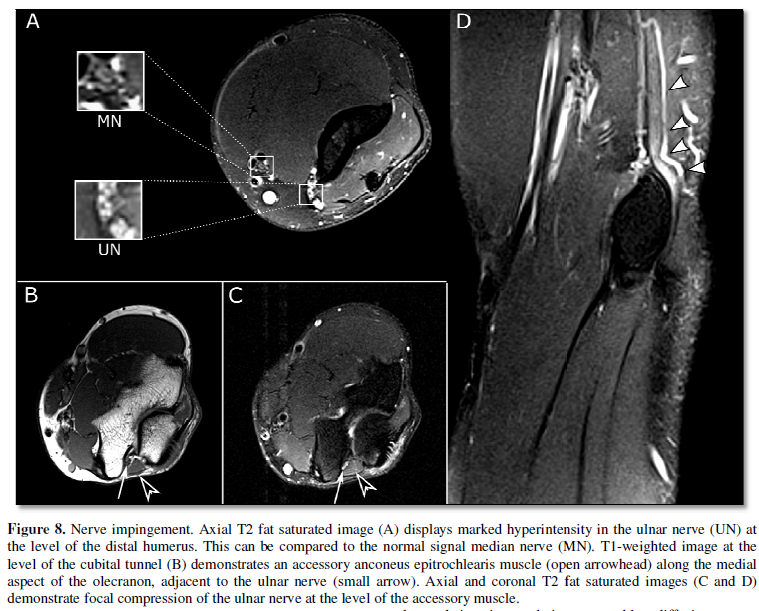

In addition to detailed

assessment of nerve pathology, MRI is essential in evaluating the surrounding

structures. Rather than direct injury to the nerve, nerve irritation can be

reactive to injury of adjacent structures (Figure

7), due to constriction by adjacent structures (Figure 8), or due to a mass. MRI can characterize these adjacent abnormalities

and establish their relationships with the nerve. This helps the surgeon to optimize

operative approach and minimize potential damage to the nerve during surgery.